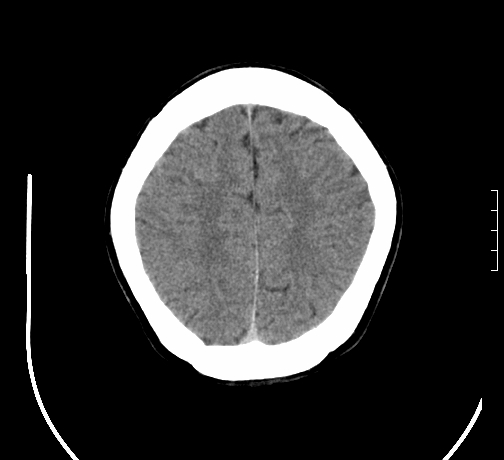

女,28岁,幼时有癫痫,常有发作,服药后可几月不发作,走路不稳3-4月,加重一月。

小脑发育畸形?

小脑萎缩。

考虑小脑发育不良,建议mri检查。

患者出现走路不稳是近几个月的事,而癫痫则有幼时就有,常发,则会常服药,癫痫药可引起小脑综合症,小脑萎缩,而小脑发育不良的主要症状不是癫痫

考虑癫痫,长期间断发服抗癫药,导致小脑综合症,小脑萎缩

不知现在还有没有癫痫,应该另有致痫灶,进一步检查。

考虑小脑发育不良伴小脑萎缩,建议mri检查。

考虑药物性小脑萎缩